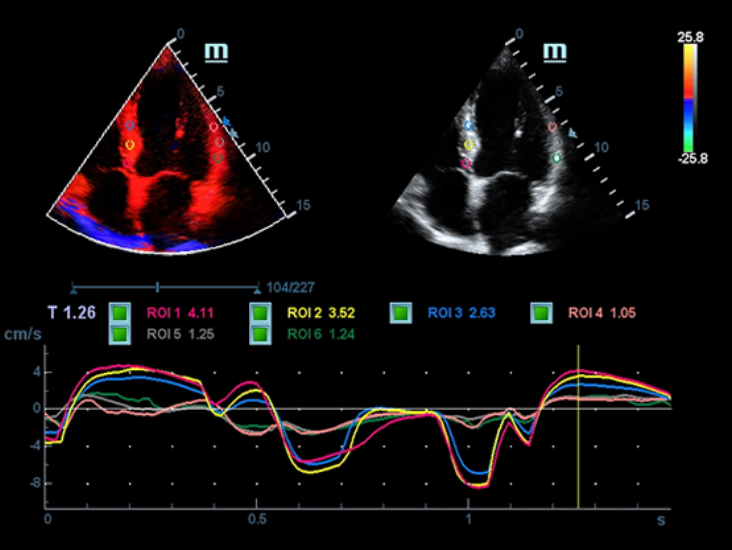

X-Insight adalah solusi untuk visualisasi lebih lanjut.

Sebagai mitra yang menyeluruh, DC-60 Exp dengan X-Insight memfokuskan dirinya untuk menghadirkan solusi yang komprehensif untuk membantu Anda mengelola semua aspek praktik klinis harian dengan mudah dan baik.

Dengan pemahaman mendalam atas kebutuhan pelanggan, DC-60 Exp dengan X-Insight dirancang untuk menyajikan efisiensi tinggi dengan pencitraan yang presisi, yang didukung oleh eXpress Clarity, eXceptional Intelligence, dan eXceeding Experience.